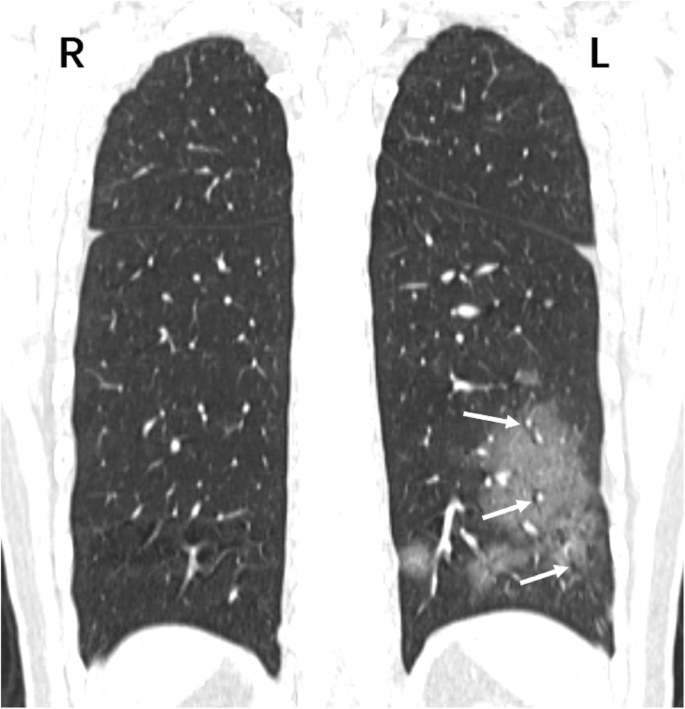

A 39-year-old female patient presenting with fever and cough, and a clear epidemiological history of contact, was admitted to our hospital. CT image shows multiple patchy GGO patterns in the lower lobes of both lungs (here, the reconstructed coronal CT image only shows lesions in the left lung). Long white arrows indicate multiple air-filled bronchi inside the lesions. NAT confirmed that the patient was infected with COVID-19. R = Right, L = Left, GGO = Ground-glass opacity, NAT = Nucleic acid test

Lesions tended to be distributed in the peripheral lung field (73.8%) (Table 2) but were seldom distributed in the central lung field (9.0%). In both groups 1 and 2, patients with involvement of the central zone were few (4 of 51 and 2 of 29 patients in groups 1 and 2, respectively), while many patients showed affected peripheral zone (21 of 51 and 25 of 29 patients in groups 1 and 2, respectively). In the peripheral zone, many lesions were adjacent to the subpleural region (284 of 548 peripheral lung lesions, accounting for 51.8%) (Figs. 2, 3, 4 and 5). In the whole lung field, the near-subpleural lesions accounted for 38.2% (284 of 743 lesions). Furthermore, the number of patients with subpleural involvement was relatively large (28 of 51 and 13 of 29 patients in groups 1 and 2, respectively).